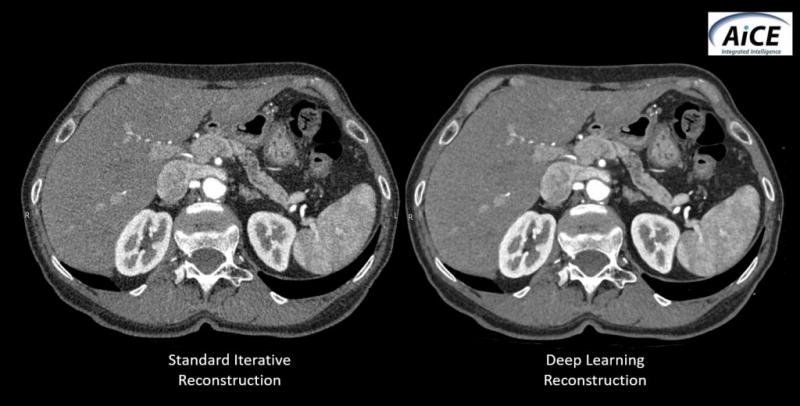

Canon showcased a smart algorithm, called the Advanced Intelligent Clear-IQ Engine (AiCE), for its ability to increase CT image resolution while minimizing patient radiation. Using deep learning technology to tell the difference between noise and signal, the AiCE algorithm “learns” to improve the resolution of CT images. It reconstructs CT images from the high-quality images produced using model-based iterative reconstruction (MBIR). Although experience with the new algorithm is limited, the company has stated that AiCE has the potential to set a new standard for image reconstruction in CT.